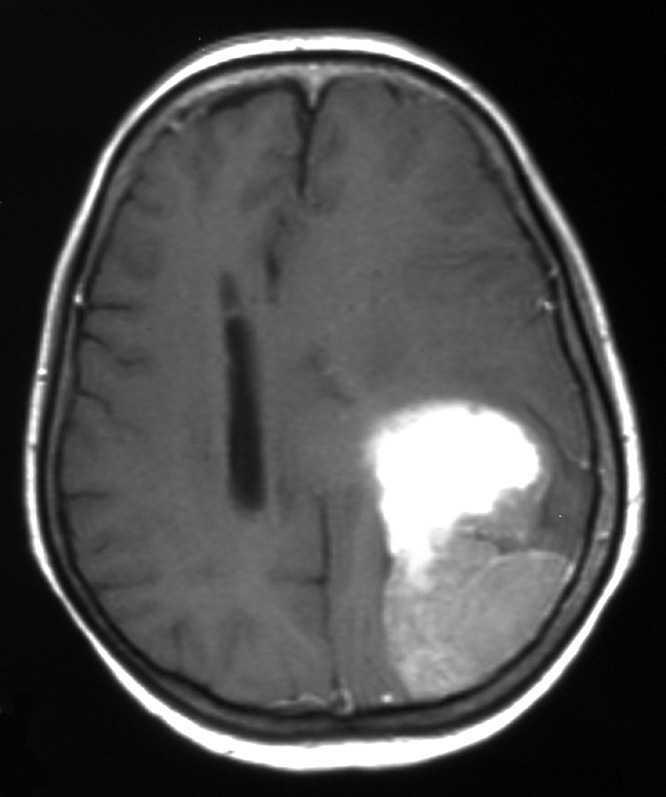

En febrero del 2002, a los 11 años del diagnóstico, la paciente consultó por un cuadro de afasia y hemiparesia derecha. Por resonancia magnética (RM) se objetivó una lesión expansiva de 8 cm temporal-occipital-parietal izquierda (figs. 2 y 3). Los marcadores tumorales fueron negativos. Dado el buen estado general de la paciente y la ausencia de enfermedad extracraneal se realizó una craneotomía con extirpación total de la lesión. El estudio anatomopatológico confirmó su naturaleza metastásica. Se efectuó radioterapia holocraneal y boost en el lecho quirúrgico (dosis total de 48 Gy), y el tratamiento finalizó en mayo de 2002. Los controles posteriores han sido negativos y la paciente se encuentra actualmente asintomática, sin secuelas neurológicas significativas y libre de enfermedad.

Figura 2. Metástasis cerebral única temporal-occipital-parietal izquierda de 8 cm.

Figura 3. Metástasis cerebral única.